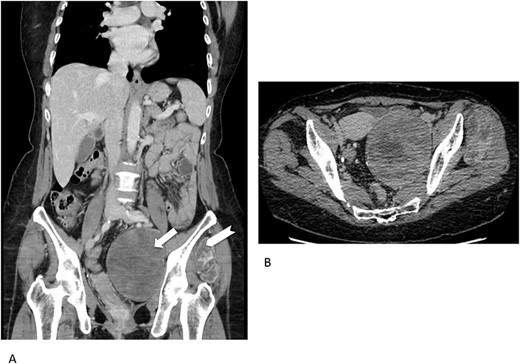

Concerning imaging description, the preliminary 64-raw MD-CT (Fig. 1) found a left-sided solid hypoattenuating, well-defined pelvic mass, with poor and inhomogeneous contrast enhancement. A similar mass coexisted in the intermuscular space between left gluteus medius and gluteus minimus.

Multidetector computed tomography appearance of the lesions. Coronal multiplanar reformation (A) of the portal venous phase scan shows two different left-sided solid hypoattenuating masses located in the pelvis (arrow) and intermuscular space between the gluteus medius muscle and gluteus minimus muscle (arrowhaed). Progressive, slow and inhomogeneous contrast-enhancement occurred (B), as better appreciated in the transverse image acquired in the delayed phase.